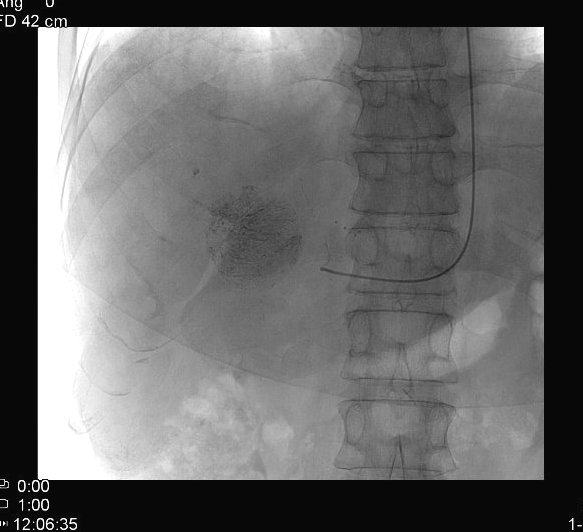

TAE (Transcatheter Arterial Embolization) and TACE (Transcatheter Arterial ChemoEmbolization) are methods with which the supplying artery/arteries of the tumor are selectively approached through the branches of the hepatic artery. When the catheter is in position the tumor branches are injected with a special, oily contrast material, Lipiodol (TAE). The injected material is used as an embolization material (figure 18.), other chemotherapeutical drugs (5-Fluoro-Uracil, Epirubicin, Cisplatin, Mytomicin-C) can also be used (TACE) (figure 19.).

Image

Figure 18. – Lipiodol uptake in HCC, selective catherarization, injection of 10 ml Lipiodol (DSA)

Figure 19. – TACE, CT control (2 weeks after treatment)

Compared to systemic chemotherapy, with these methods 10 or even 100 times greater drug concentrations can be delivered to the tumor tissue. Moreover, due to the effects of Lipiodol, the drug effects persist longer, while normal liver parenchyma will wash out the chemicals faster leaving little or no harm.

This can be successfully combined with the other percutaneous methods, especially during the treatment of multiplex primary and secondary tumors.